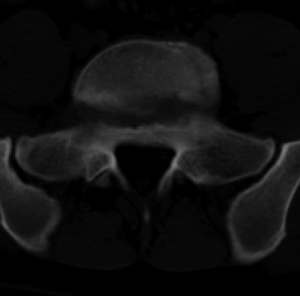

男,20,士兵,腰痛3年多,无外伤史

考虑:1、多发许莫尔氏结节形成;

倒数7~9幅图像示椎体后缘双边征及双关节征,支持l5轻度滑脱。

1、多发许莫尔氏结节形成;

2、椎弓峡部断裂。

3、l5轻度滑脱。

1、多发许莫氏结节。

2、腰5双侧椎弓峡部崩裂并i度前滑脱,楼主椎间盘扫描角度有问题,另外需要反倾角扫描腰5椎弓峡部。

2、腰5双侧椎弓峡部崩裂并i度前滑脱。